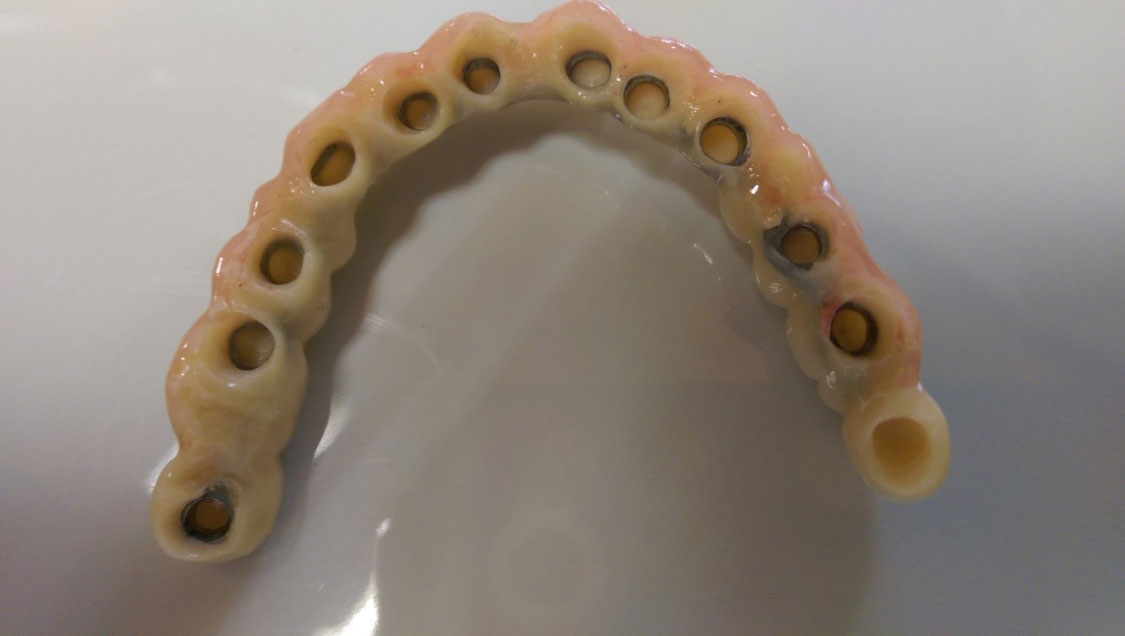

• esettanulmany-40

Így néz ki a hosszútávú ideiglenes híd.(Fém vázzal erősített műanyag híd.)

• esettanulmany-41

Így néz ki a hosszútávú ideiglenes híd. (Fém vázzal erősített műanyag híd.)

• esettanulmany-42